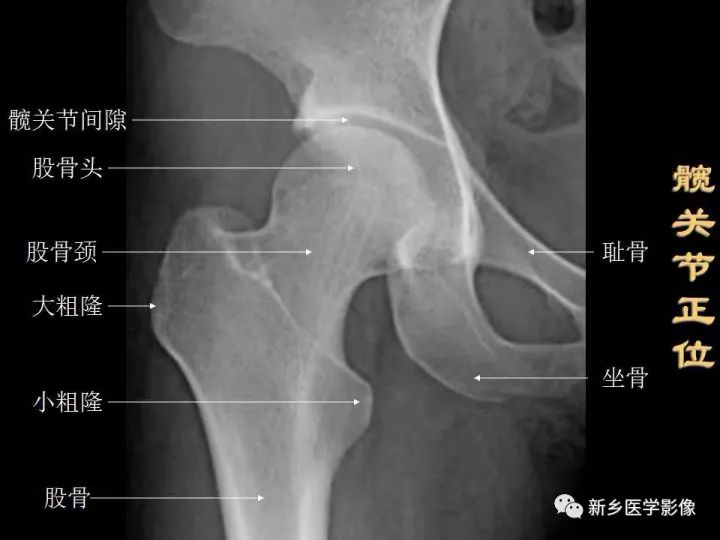

髋关节的X线解剖

常规拍摄正位(见图1)和侧位X线片。正位线片上,因髋臼三骨之间以“Y”形软骨相连,融合之前,表现为横行带状透亮影,其宽窄随着年龄变化而改变。年龄越小此透亮带越宽;年龄越大,透亮带变窄,15~17岁左右消失。股骨头大部套在髋臼内,表面光滑,为致密的细弧线。头的中心偏后下部有一小凹陷,是股骨头凹,有时可投影到股骨头弧线内侧,显示为小环形透亮圈。侧位片上,中央的凹窝是髋臼,呈半圆形的致密线。

图1 骨盆正位片